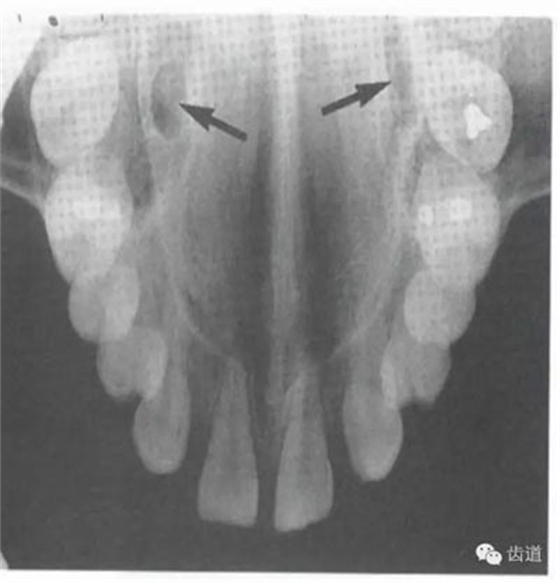

鼻腔位于上切牙根尖的上方,顯示為對(duì)稱性半圓形密度低的影像,其中間被一密度高的骨隔分開(kāi)為鼻中隔

在兩個(gè)中切牙牙根之間或稍上方,多呈橢圓形密度低的影像,切牙孔影像可重疊在一側(cè)中切牙牙根尖處,易誤認(rèn)為根尖周病變,可視牙周膜和骨硬板是否完整加以鑒別